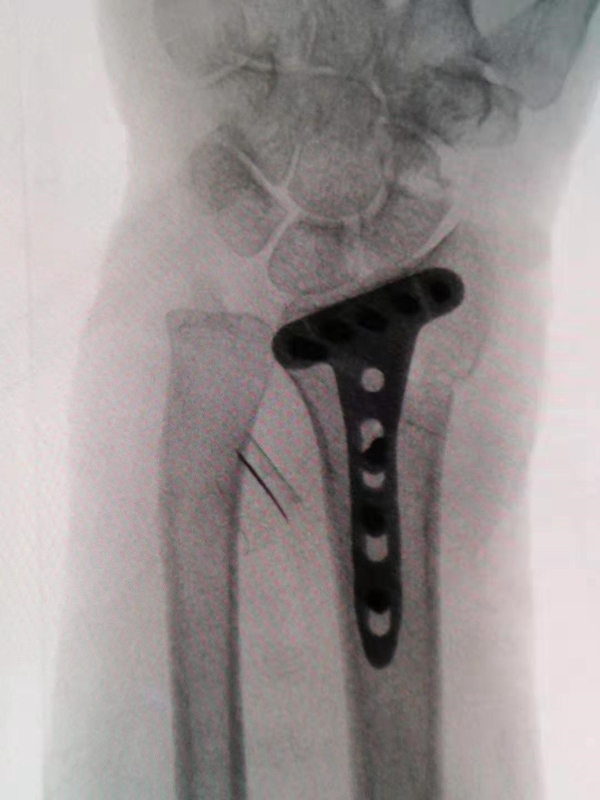

A、标准:螺钉的长度刚刚好到对侧皮质却不穿过对侧皮质,钢板高度刚好到分水岭又没有高于分水岭,螺钉角度紧贴关节面但又没有穿入关节。

F、由于掌侧端骨皮质较多,一般复位后先在远侧骨折块两侧打入2枚克氏针临时固定,直视及C臂透视确认掌侧复位满意后选择低切迹钢板或微型钢板固定。

如骨折块较小微型钢板无法有效固定,则选择掌侧低切迹钢板做掌侧“框架“固定,但放置高度不得超过“分水岭“解剖标志,对单纯桡骨极远端骨折涉及关节面但无明显塌陷病例,先前打入的2枚克氏针根据情况剪断后即可有效固定。

G、克氏针主要经钢板穿3个方向:月骨窝、桡骨茎凸及横向或纵向固定(适用于十分粉碎或下尺桡关节损伤的患者)。骨折越复杂应用的克氏针越多,如果与螺钉打架,则更换克氏针。

H、置放钢板的位置十分重要,要注意尽量靠近远端,但不能超过分水岭;一般放置在分水岭稍微靠近端2mm,若太远端虽然可以防止边缘的骨折移位,但则需要用万象锁定螺钉,调节角度打钉,否则很容易穿进关节。

图8 钢板放置于分水岭近侧2mm